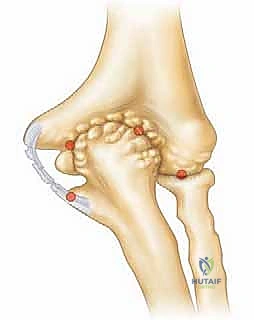

وبشكل محدد، يؤدي هذا الترهل إلى انحشار عظمي مباشر وعنيف بين الجانب الخلفي الإنسي من الناتئ المرفقي (Olecranon) والحفرة المقابلة له في عظم العضد (Olecranon Fossa). هذا الاحتكاك القوي والمتكرر هو أصل المرض، وهو ما يؤدي إلى تفتت الغضروف ونمو زوائد عظمية مؤلمة (Osteophytes) تعيق حركة فرد الكوع تماماً.

يمكن أن يؤدي الانحشار العظمي المزمن، كما هو الحال في متلازمة إجهاد الكوع الانقلابي، إلى إصابات غضروفية كبيرة – أي تلف وتآكل في الغضروف المفصلي الناعم الذي يغطي نهايات العظام – بالإضافة إلى تكوين نتوءات عظمية تفاعلية (Spurs) داخل الجزء الخلفي من المفصل.

وهذا هو السبب في أن سلامة الرباط الجانبي الزندي (UCL) أمر بالغ الأهمية. يتكون هذا الرباط من حزم أمامية وخلفية ومستعرضة، وتعتبر الحزمة الأمامية هي خط الدفاع الأول ضد قوى الانقلاب. عندما يضعف هذا الرباط، تفقد العظام مسارها الصحيح، ويبدأ الناتئ المرفقي (Olecranon) بالاصطدام بجدران الحفرة المرفقية، مما يخلق النتوءات العظمية التي تميز متلازمة إجهاد الكوع الانقلابي.

4. إزالة النتوءات العظمية (Osteophyte Excision):

هذه هي الخطوة الأكثر دقة وحساسية، وهنا تتجلى خبرة الأستاذ الدكتور محمد هطيف. باستخدام أدوات دقيقة (Burr)، يقوم بنحت وإزالة النتوءات العظمية الخلفية التي تسبب الانحشار.

تحذير جراحي هام: يؤكد الدكتور هطيف دائماً على قاعدة جراحية ذهبية في هذه العملية: "يجب إزالة العظام الزائدة فقط (النتوءات)، ويجب عدم المبالغة في إزالة جزء من العظم الأصلي للناتئ المرفقي". لماذا؟ لأن الإفراط في إزالة العظم سيؤدي إلى فقدان المفصل لاستقراره العظمي، مما يضع ضغطاً مضاعفاً ومميتاً على الرباط الجانبي الزندي (UCL)، وقد يؤدي إلى تمزقه بالكامل لاحقاً. هذه الدقة في تحديد "كمية العظم المزال" هي ما يميز الجراح الخبير عن غيره.